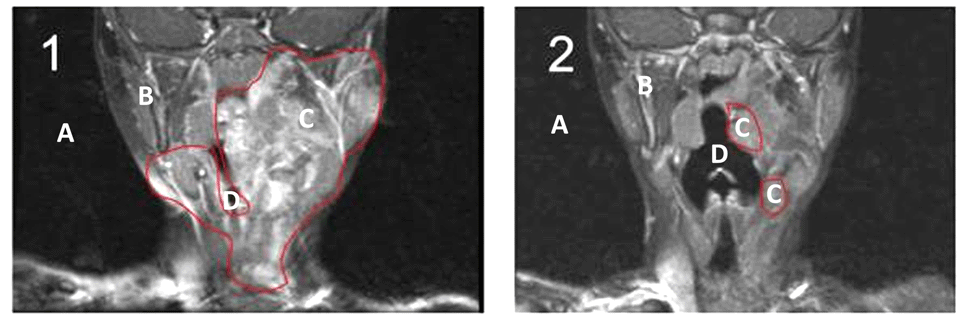

Sei que nem todos entendem imagens radiológicas, mas as figuras abaixo são ressonâncias magnéticas de parte da cabeça e do pescoço, vistas de frente e que foram realizadas antes (1) e depois (2) do tratamento com imatinibe durante 3 meses.

A área mais escura (A) é ar ao redor da cabeça ou dentro das vias aéreas (D), a área cinza é o corpo da menina (B) e a área mais clara (C) circundada por uma linha vermelha é o neurofibroma plexiforme.

Acho que todos podem ver que a área dentro da linha vermelha (C) ficou menor na segunda ressonância (2), realizada depois do tratamento com o imatinibe. É possível observar como o espaço aumentou na via aérea (D), permitindo melhor respiração e sono.